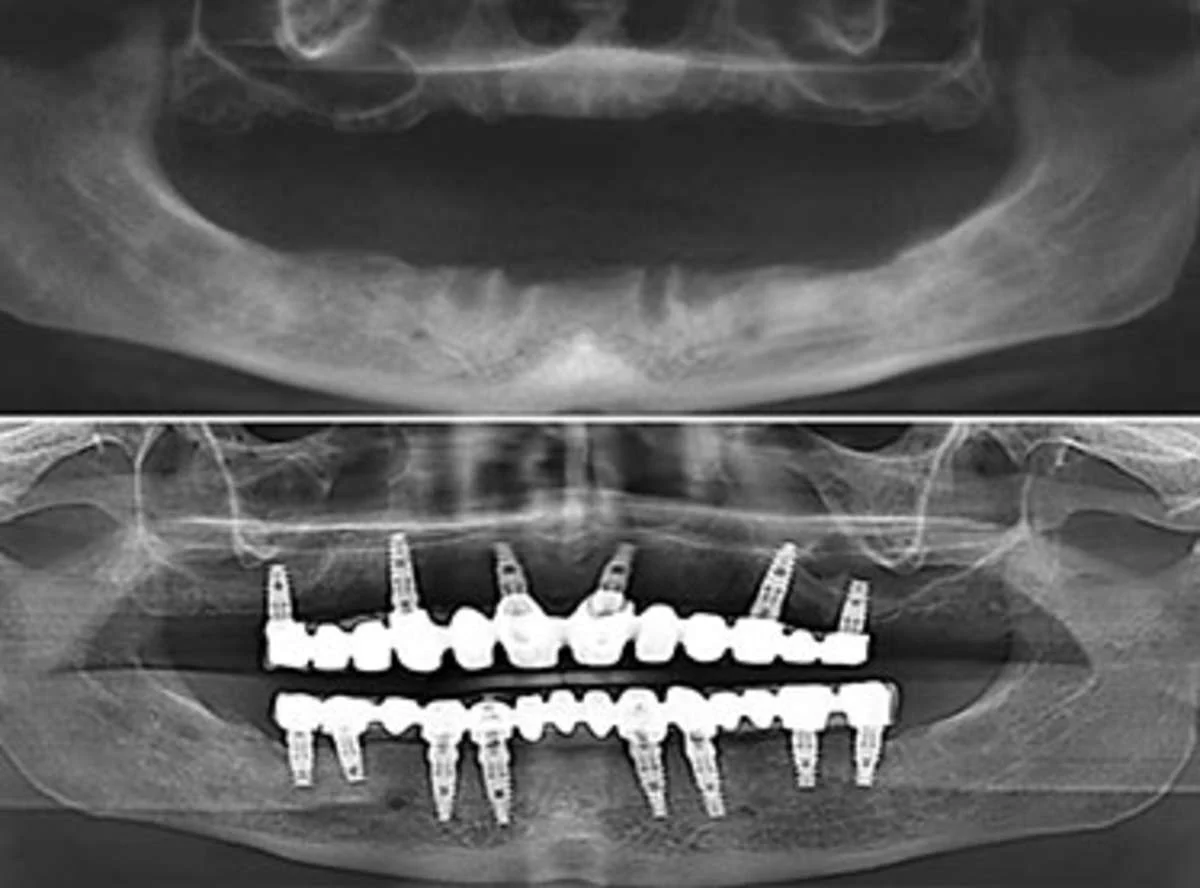

Gli impianti dentali All-on-8 rappresentano una delle soluzioni più avanzate e stabili per la riabilitazione totale dell’arcata dentale. Questa tecnica prevede l’inserimento di otto impianti per ogni arcata, posizionati strategicamente nell’osso mascellare o mandibolare, allo scopo di sostenere un ponte fisso che rimpiazza tutti i denti mancanti.

- A differenza dei sistemi All-on-4 o All-on-6, l’All-on-8 garantisce un livello superiore di supporto e distribuzione del carico masticatorio, grazie all’aumento del numero di impianti utilizzati.

- Gli otto impianti dentali fungono da ancore per una protesi fissa di 12-14 elementi, permettendo di ritrovare una masticazione efficace e un sorriso naturale.

- Valutazione iniziale e diagnostica avanzata: il dentista effettua un’analisi approfondita con radiografie panoramiche e scansioni 3D per studiare la morfologia ossea e pianificare il posizionamento degli impianti.

- Posizionamento degli impianti: sotto anestesia locale (o sedazione, se richiesta), vengono inseriti otto impianti dentali con inclinazioni strategiche per sfruttare al meglio l’osso disponibile.